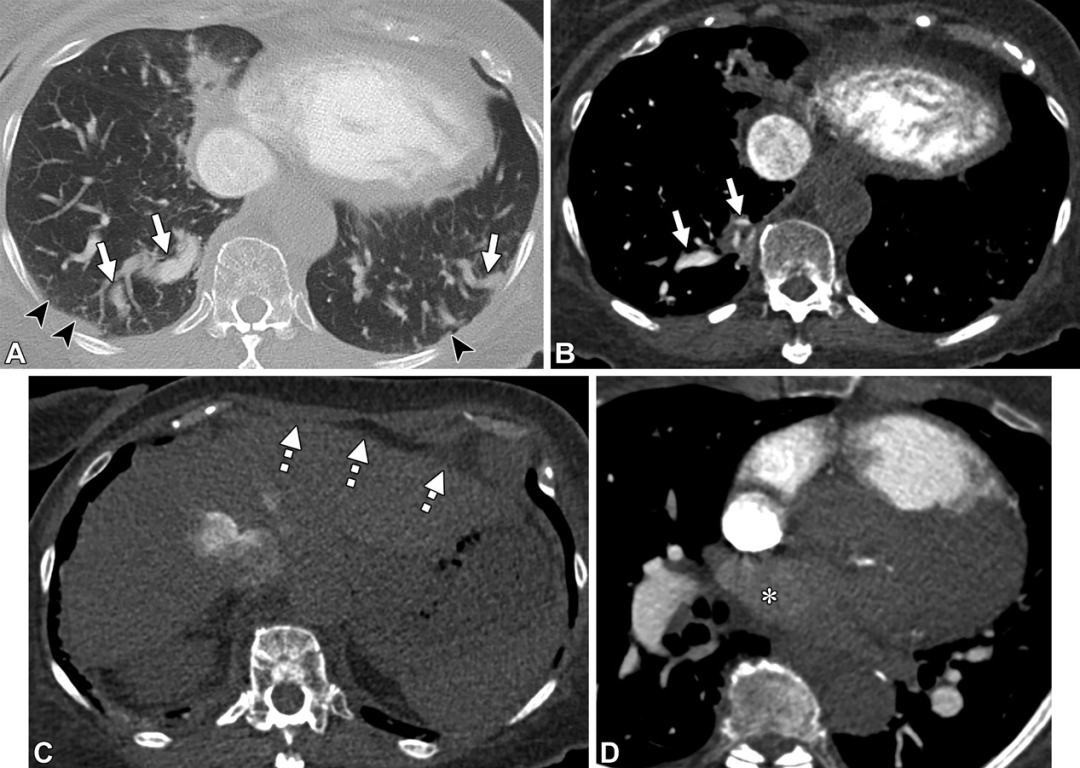

PAVM。轴位CT图,32岁男性,遗传性出血性毛细血管扩张症,因右向左分流导致的慢性低氧血症。(A,B)轴位CT图,可见右肺下叶PAVM的病灶(白色信号)及引流静脉(白色箭头)。(C,D)轴位CT图,可见供血动脉大于3mm(白色箭头)。(E)右肺下叶另见一个PAVM,在供血动脉及引流静脉之间的磨玻璃密度影(白色圆圈),提示显微镜下毛细血管扩张。(F,G)一个复杂的PAVM位于左肺下叶,可见三个供血动脉(F图中白色虚线箭头)以及一个粗大的引流静脉(白色星号),注意观察引流静脉比供血动脉大。